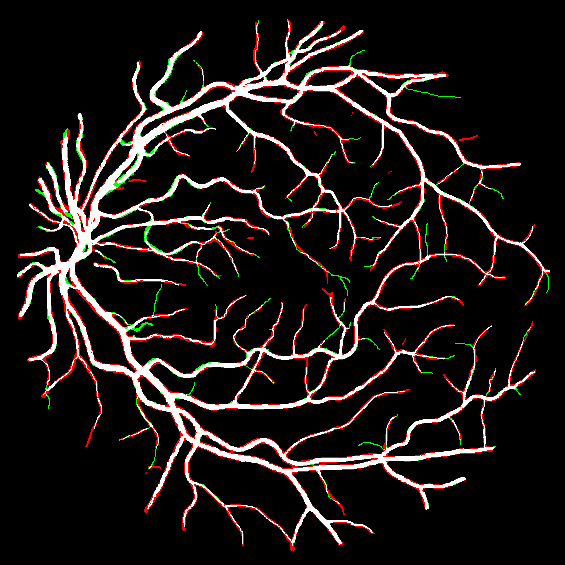

To justify the performance of our model, we compare the 4 metrics with 8 representative previous works from all 3 open-access datasets. The comparison results presented in Table 1 show that our MP-Net model outperforms the state-of-the-art methods regarding accuracy and in all three datasets, which meter the practical prediction quality and the overall prediction quality independent on thresholding specifications. The advancement is greater in the DRIVE dataset. It’s related to the fact that the DRIVE dataset contains more thin vessels, which is the main target of our model. Specificity is also the highest in DRIVE and CHASE_DB1 while sensitivity is highest in STARE. Particularly, our method outperforms ML-UNet [2] and JL-UNet [4] which adopt a different multi-class approach to also especially tackle the thin-vessels challenge. Figure 2 shows an example of our segmentation maps on DRIVE. As can be seen, most thin vessels and boundary areas have been meticulously picked up.